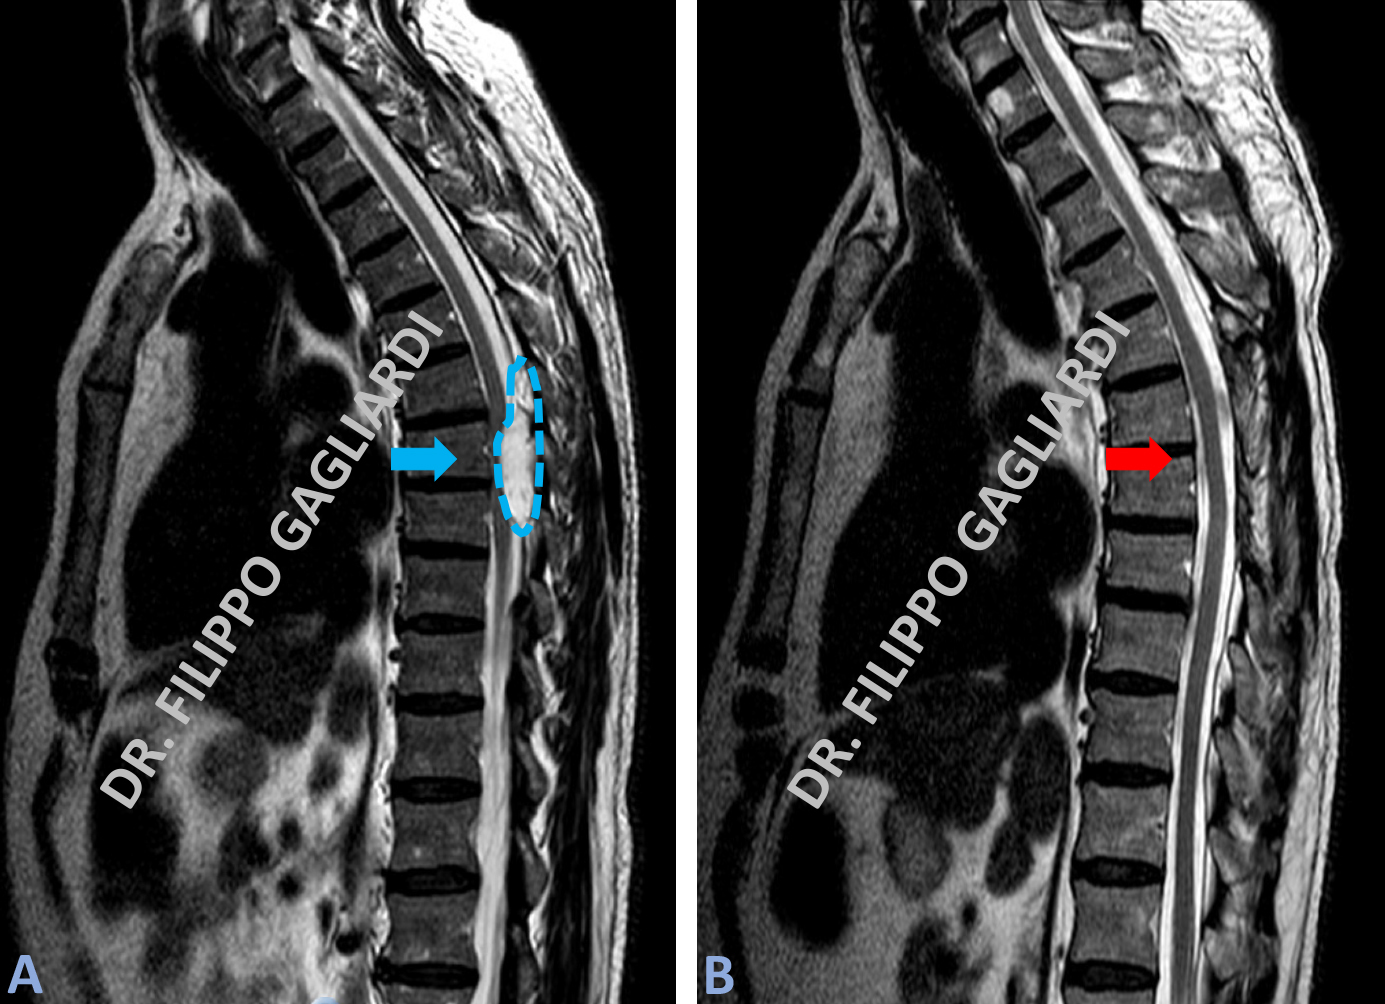

meningioma dorsale Caso di meningioma dorsale. Il tumore disloca in avanti e comprime il midollo spinale (frecce azzurre Figura A e B). Il Paziente è stato sottoposto ad intervento di laminectomia (apertura del canale vertebrale) ed asportazione del meningioma. La RM di controllo post operatoria documenta l’asportazione totale della massa e la conseguente decompressione del midollo spinale (frecce rosse Figure C e D).